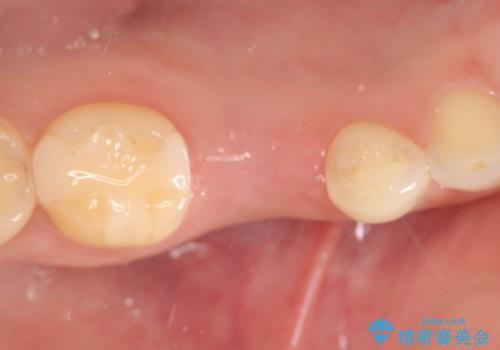

残せなくなってしまった乳歯 インプラントによる補綴

- 大人になっても残っていた乳歯が噛むと痛くなり、治療を求めて来院されました。

残す手段を検討しましたが大きな虫歯・根尖病変の存在し、大きく歯ぐきも腫れ炎症も強く認められる状態を改善するため抜歯を行いインプラントによる咬合機能回復を計画します。